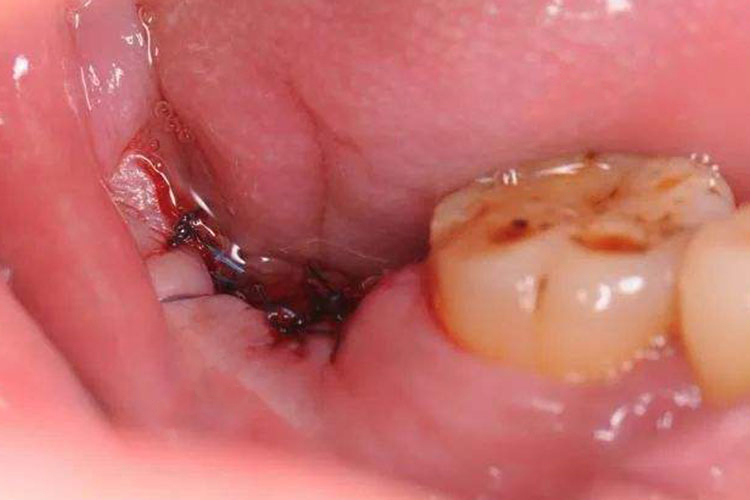

干槽症一般发生在拔牙2~3天后,以下颌后牙多见,其主要表现为创口周围牙龈红肿,牙槽内有散发恶臭味的腐败血凝块,有时会有灰白色伪膜覆盖,严重者牙槽空虚,骨面外露。此外,创口处剧烈疼痛,可向耳颞部、下颌及头顶处放射,下颌下淋巴结也受累肿大、压痛等。

结合患者的拔牙手术史,根据患者的症状表现进行确诊,如术后牙槽空虚、槽窝内腐败恶臭味的血液凝块、创口剧烈疼痛等。

干槽症的治疗原则是清创、止痛,隔离外界对牙槽窝的刺激,促进肉芽组织的生长。通常是在麻醉后用3%过氧化氢溶液清洗,去除腐败坏死物质,在牙槽窝内放入碘仿纱条,添加促进肉芽组织生长的药物(如康复新液),一般8~10天后取出碘仿纱条,牙槽内已有一层肉芽组织覆盖,伤口会逐渐愈合。